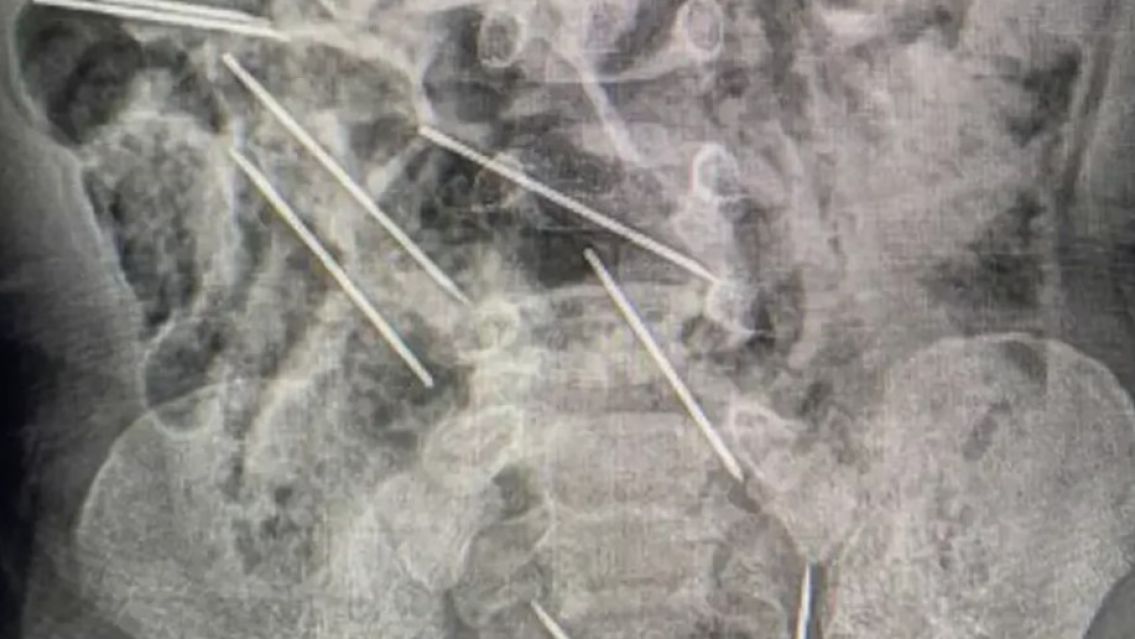

Los médicos tardaron dos horas en extraer las piezas metálicas que se habían alojado en el estómago.

La compleja operación llevó aproximadamente dos horas, ya que las agujas estaban diseminadas en el estómago y el tracto intestinal del niño. Durante la cirugía, los especialistas describieron cómo localizaron los objetos metálicos una vez que abrieron el abdomen del niño. Uno de los médicos compartió su experiencia con esta delicada intervención: "Dos de las agujas se encontraban en una posición peligrosa entre la vejiga y el recto, lo que hizo que la operación fuera extremadamente arriesgada".